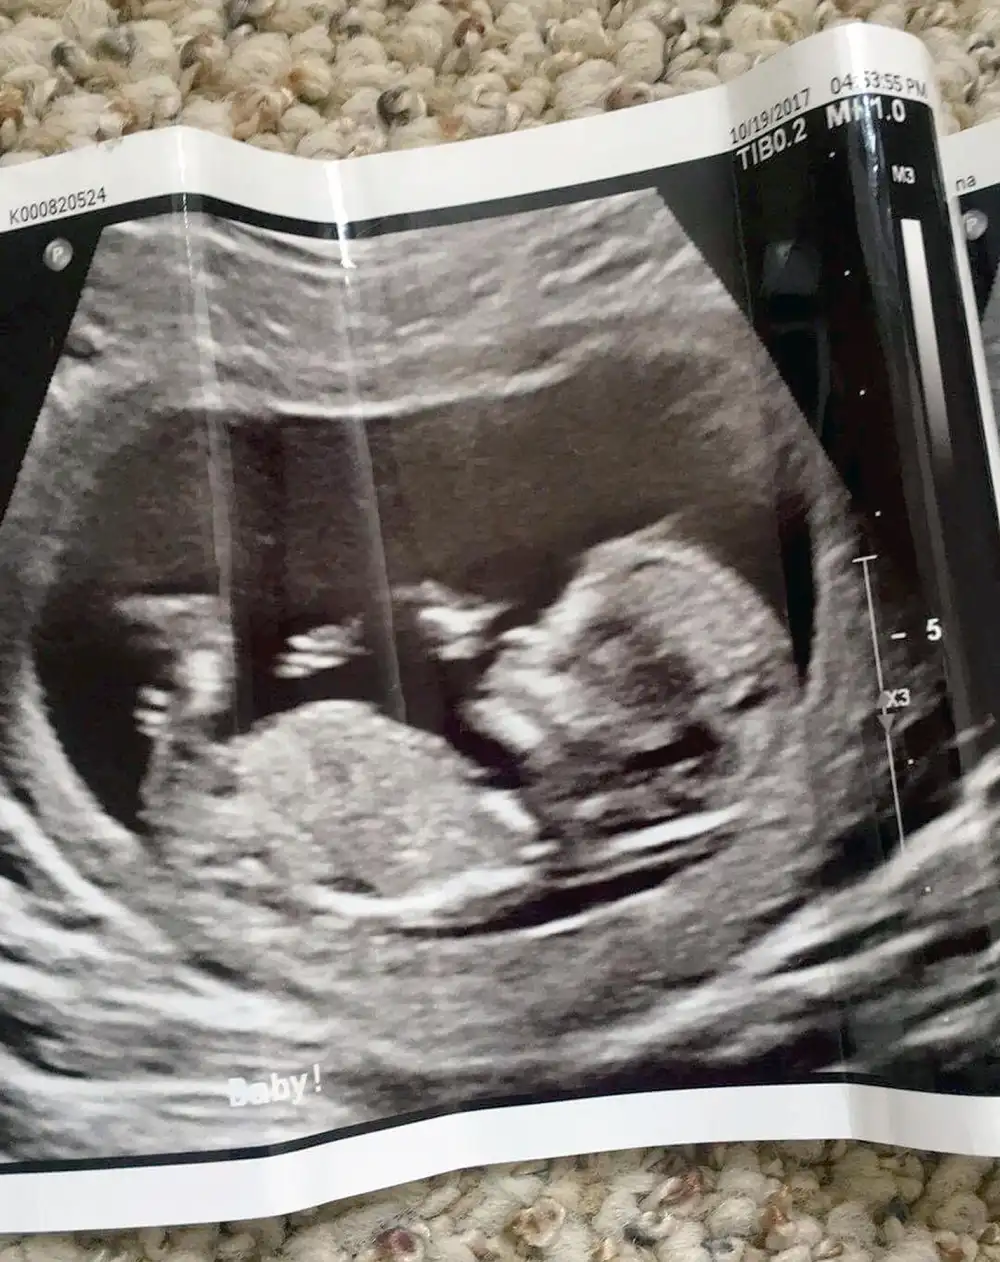

Though Stephens tells Us she has only gained five pounds — “it went to my breasts!” — she has regular ultrasounds and her little boy is the perfect weight and length.